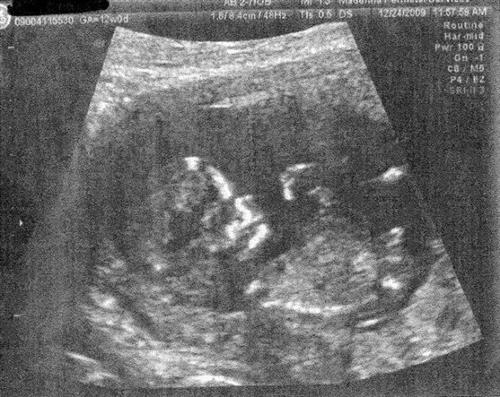

12 weeks